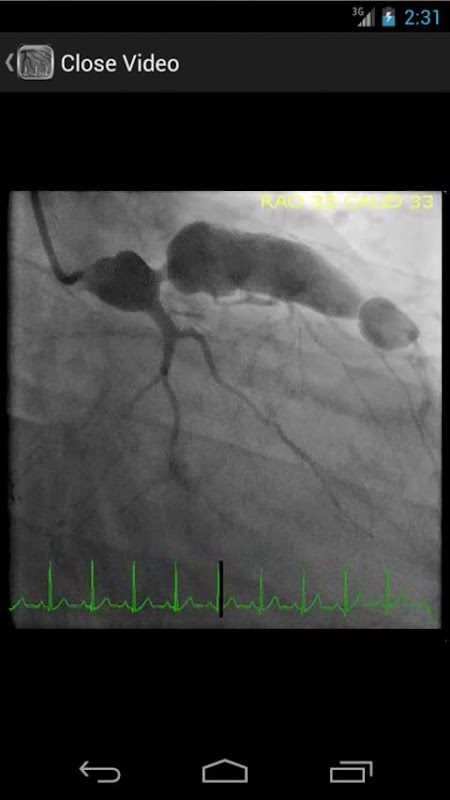

* Banco de dados contendo mais de 30 vídeos (angiografias coronárias, ventriculogramas e aortograms) de ambos os achados comuns e raras no laboratório de cateterismo cardíaco